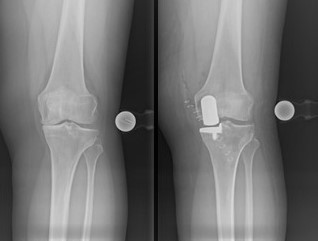

Die Behandlungen im Endoprothetik-Zentrum zielen darauf ab, das natürliche Gelenk eines Patienten zu bewahren. Nach einer umfassenden Diagnostik werden zunächst konservative Behandlungsmöglichkeiten ausgeschöpft. Zudem werden gelenkerhaltende Operationen angeboten. Bei fortgeschrittener Gelenkschädigung hilft oft nur ein künstlicher Gelenkersatz. Mit gewebeschonenden Implantationsverfahren, können individuelle maßgeschneiderte Implantate und Sonderprothesen eingesetzt werden.

Treten nach einer Implantation einer Prothese Beschwerden auf oder sind ursprüngliche Beschwerden nicht ausreichend behandelt, muss nach der Ursache gesucht werden. Körperliche Untersuchungen, Röntgenanalysen und bei Bedarf spezielle Zusatzuntersuchungen (diagnostische Punktion, MRT, etc.) liefern die Basis für die weiterführende Behandlung. Aufgrund unserer langjährigen Erfahrung kann in den meisten Fällen die Ursache analysiert und eine adäquate Therapie eingeleitet werden.